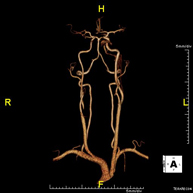

Prova diagnòstica no invasiva que consisteix en l'estudi vascular del sector aorto-ilíac i dels vasos arterials de les dues extremitats inferiors, am l'obtenció d'imatges d'alta definició anatòmica mitjançant l'ús d'un camp electromagnètic i ones de ràdio (amb un emissor i un receptor). És indispensable l'ús de contrast paramagnètic (Gadolini). No obstant, no utilitza radiació ionitzant. La qualitat de les imatges permet realitzar reconstruccions en 2D i 3D. Està especialment indicat en aquells pacients en els que hi ha sospita de malaltia vascular a les dues extremitats, en pacients amb malaltia vascular de les dues extremitats com a mapa vascular abans del tractament (percutani o quirúrgic), com a mapa vascular prequirúrgic en pacients amb lesions òssies o musculars que requereixin cirurgia, etc. - Angio-RM d'Artèries renals

Prova diagnòstica no invasiva que consisteix en l'estudi de l'artèria aorta abdominal per obtenir imatges d'alta definició anatòmica mitjançant l'ús d'un camp electromagnètic i ones de ràdio (amb un emissor i un receptor). És indispensable l'ús de contrast intravenós paramagnètic (Gadolini). No obstant, no utilitza radiació ionitzant. La qualitat de les imatges permet realitzar reconstruccions en 2D i 3D. Està especialment indicada en pacients amb sospita de malaltia vascular de les dues extremitats, en pacients amb malaltia vascular de les dues extremitats com a mapa vascular abans del tractament (percutani o quirúrgic), com a mapa vascular prequirúrgic en pacients amb lesions òssies o musculars que requereixin cirurgia, etc. - Angio-RM Lesió de parts toves